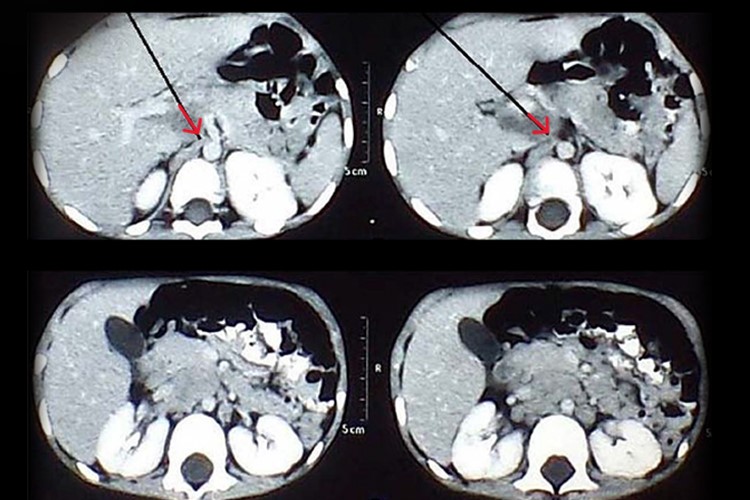

腹膜间皮瘤早期无明显症状,后期表现为腹水、腹部肿块、腹痛、腹胀、胃肠道症状以及全身不适等。腹部超声检查可见腹膜不规则增厚、实质性肿块改变、腹水、腹膜后淋巴结肿大、肠系膜增厚等。